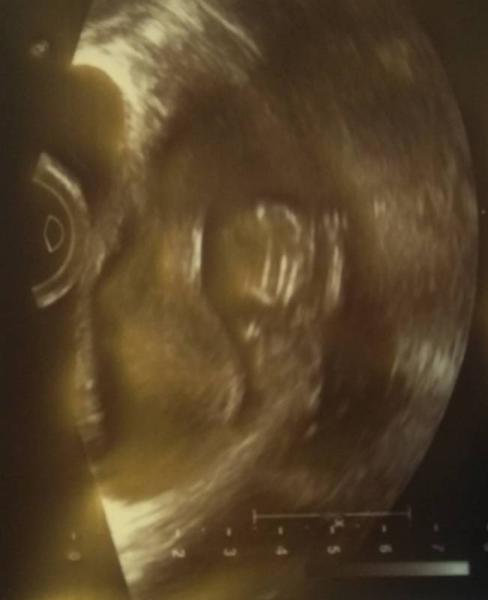

So, ich komme gerade vom Arzt und es ist alles bestens der Zwerg ist 4,7 cm groß und war fleißig am turnen. Es ist schon verrückt, dass man die Bewegungen sehen aber noch nicht spüren kann. Ich bin so unendlich erleichtert! Auf dem.Bild hebt es gerade den Arm und grüßt euch alle ganz herzlich

Bild zu Heute Termin bei 11+2 / Auflösung Schrödingers Baby - Forum für April - Mamis